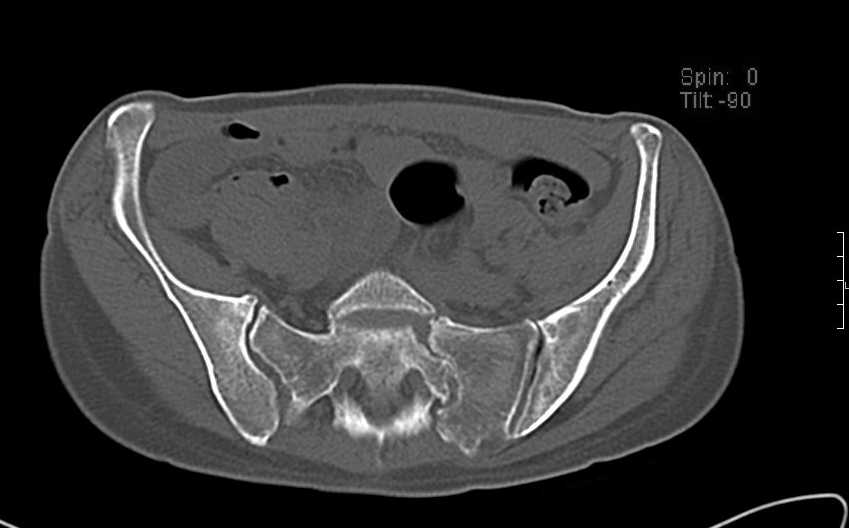

Больная 43 года (промышленный альпинист), 28.07.08 в результате падения с 5 этажа получила политравму:

Перелом свода и основания черепа. Вертикально-нестабильное повреждение таза, осложнённое разрывом мочевого пузыря. Чрезвертельный перелом левого бедра. Перелом правой таранной кости, переломовывих правой кубовидной кости. Тупая травма живота, разрыв печени, ушиб почек. Забрюшинная гематома. В день травмы - лапаротомия, ушивание ран печени. Разрыв мочевого пузыря не диагностирован. Течение болезни осложнилось развитием мочевого затёка и обширной пред- и забрюшинной флегмоны, сформировался свищ мочевого пузыря. 19.8.2008 вскрытие, дренировние флегмоны, ревизия мочевого пузыря, обтурация мочевого свища (свищ закрылся в октябре), 1.10.2008 некрэктомия, пластика по Шеде-Лидскому правой кубовидной кости. По результатам КТ диагностирован рак правой почки (диагностическая находка), 8.10.2008 нефрэктомия справа.

Переломы велись консервативно.

Имеется вертикальное смещение левой половины таза с выраженным отведением крыла (клинически подвижности нет), несросшийся низкий двухколонный перелом левой вертлужной впадины с потерей конгруэнтности, укорочение около5 см, застарелый разрыв лонного сочленения, неправильно сросшиеся переломы обеих ветвей правой лонной кости с укорочением, патологическая подвижность лоно-седалищного фрагмента слева. Правая нижняя конечность неопорна, несмотря на то, что лежа прямую ногу поднимает, ходит на левой ноге (ортопедическая обувь) с костылями, справа тазобедренный ортез. Седалищные нервы работают.Урологи отпустили больную на 6 мес.